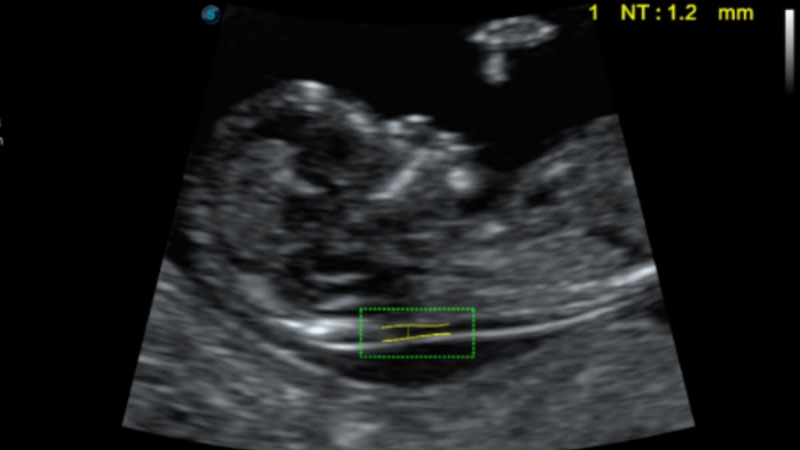

S-Fetus基于大數(shù)據(jù)深度學(xué)習(xí)算法,能夠幫助您在產(chǎn)前篩查過程中智能識(shí)別胎兒標(biāo)準(zhǔn)切面、自動(dòng)測(cè)量并錄入報(bào)告。一個(gè)按鍵,即可智能、精準(zhǔn)、高效地獲取胎兒生理指標(biāo),極大簡化您的產(chǎn)科檢查操作。

可快速對(duì)產(chǎn)科掃查切面完成胎兒生理學(xué)參數(shù)的自動(dòng)測(cè)量,減少操作者按鍵次數(shù),大幅提升檢查效率。

自動(dòng)識(shí)別頸項(xiàng)透明層并獲得NT值,為早孕胎兒畸形篩查提供有效測(cè)量工具,提高診斷效率和診斷信心。